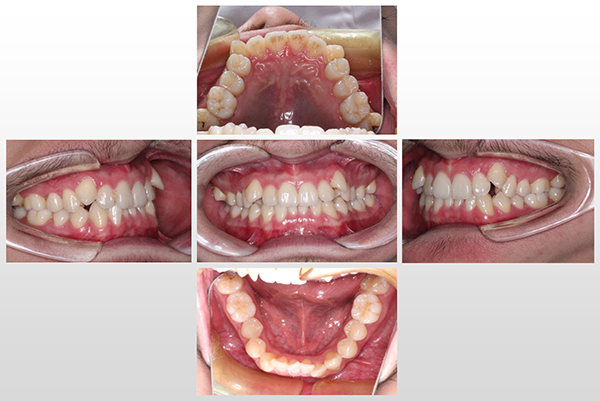

此前,我院正畸修复团队接到了一个下级医院的转诊病例,患者是一个前牙区重度拥挤的13岁小患者,他此前就诊的医院均要求拔除四个第一前磨牙和四个智齿共计八颗牙齿才能矫正。小患者的父母四处求医希望尽量少拔牙,而小患者也只想选择隐形矫正,这就对医生的技术要求极高。最终,小患者一家人选择来到柳州市人民医院就医。

治疗前

经多次会诊后,我院正畸修复团队、口腔外科团队、口腔内科团队联合制定治疗方案——只拔除四个智齿不拔除正常好牙,推磨牙向远中的隐适美无托槽隐形矫正,由口腔外科团队为小患者在颧牙槽嵴和外斜线上下颌四个位置各种植了一枚微螺旋种植钉,口腔内科团队为患者做了牙周维护,防止种植钉发炎,正畸修复团队经过近四年的努力终于排齐了牙齿,完成了高难度的牙齿移动,患者得到了满意的疗效。

治疗后